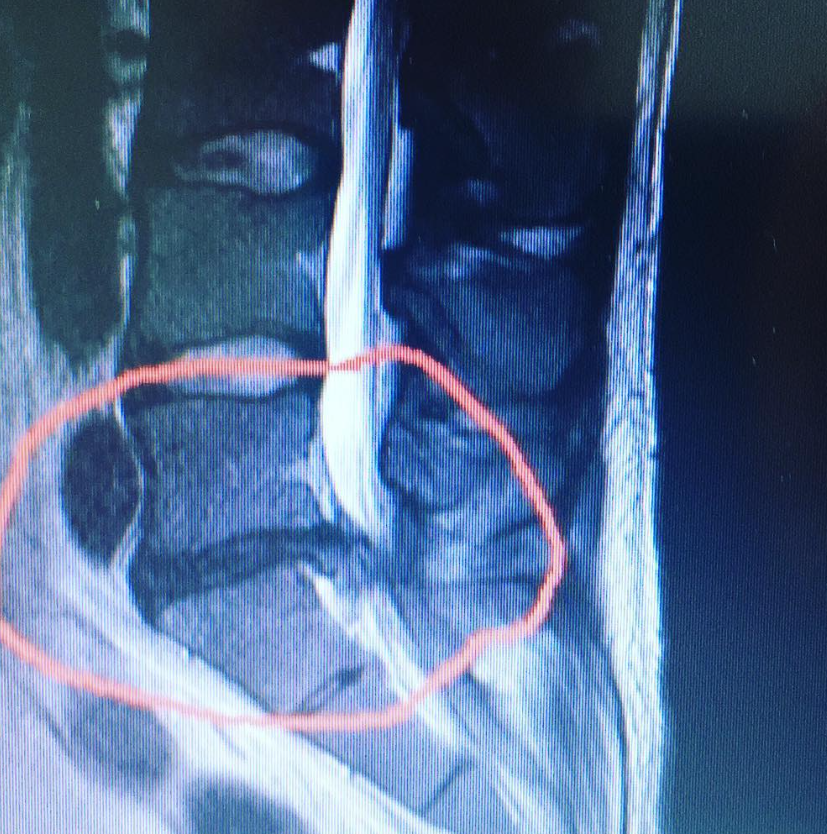

The f**k is dat?

Hernia

Dat stukje weefsel is van de hernia?

Unkown muscle mass, unlock je na 10 jaar blasten.Dat stukje weefsel is van de hernia?

Maar wat is het?